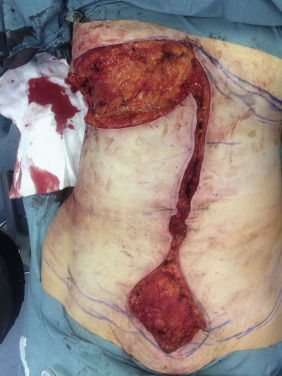

Inframammary Fold Resection ( Fig. 32.4 )

The upper abdominal resection removes the dog-ear created by the midline closure and allows the lateral excess skin at the level of the IMF to be resected. It can be continued as far laterally as necessary. Tailor tacking is used to establish the amount of tissue resected. The length of the inferior resection margin should correspond to the length of the upper abdominal incision.